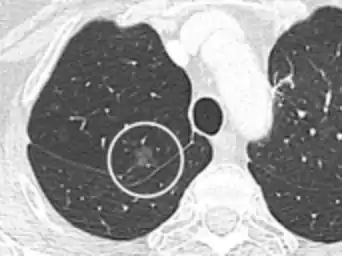

• Location: Upper lobe location is a risk factor for cancer, while a location close to a fissure or the pleura indicates a benign lymph node,[8] especially if having a triangular shape.[9]

• Margin morphology: a spiculated margin is a risk factor for cancer.[8] Benign causes tend to have a well defined border, whereas lobulated lesions or those with an irregular margin extending into the neighbouring tissue tend to be malignant.[10] In particular, spiculations are highly predictive of malignancy with a positive predictive value up to 90%.[9] Also, a "notch sign", which is an abrupt indentation of the nodule, increases the risk of cancer, but may also be found in granulomatous diseases.[9]

Calcifications and popcorn-like appearance, conferring a diagnosis of hamartoma.[9]

• In case of calcifications, a popcorn-like appearance indicates a hamartoma, which is benign.[3]

• Pleural retraction is far more common in cancers.[9] It is the pulling of visceral pleura towards the nodule.[9]

Lung nodule abutting a pulmonary cyst.[9]

• A lung nodule abutting a pulmonary cyst is a rare finding, yet indicating cancer.[9]

• Bubble-like lucencies in the nodule indicate cancer:[9]

Thin slice and maximal intensity projection of a lung nodule, the latter better visualizing vascular convergence.[9]

• Vascular convergence is where vessels converge to a nodule without adjoining or contacting the edge of the nodule, and is mainly seen in peripheral subsolid lung cancers.[9] It reflects angiogenesis.[9]